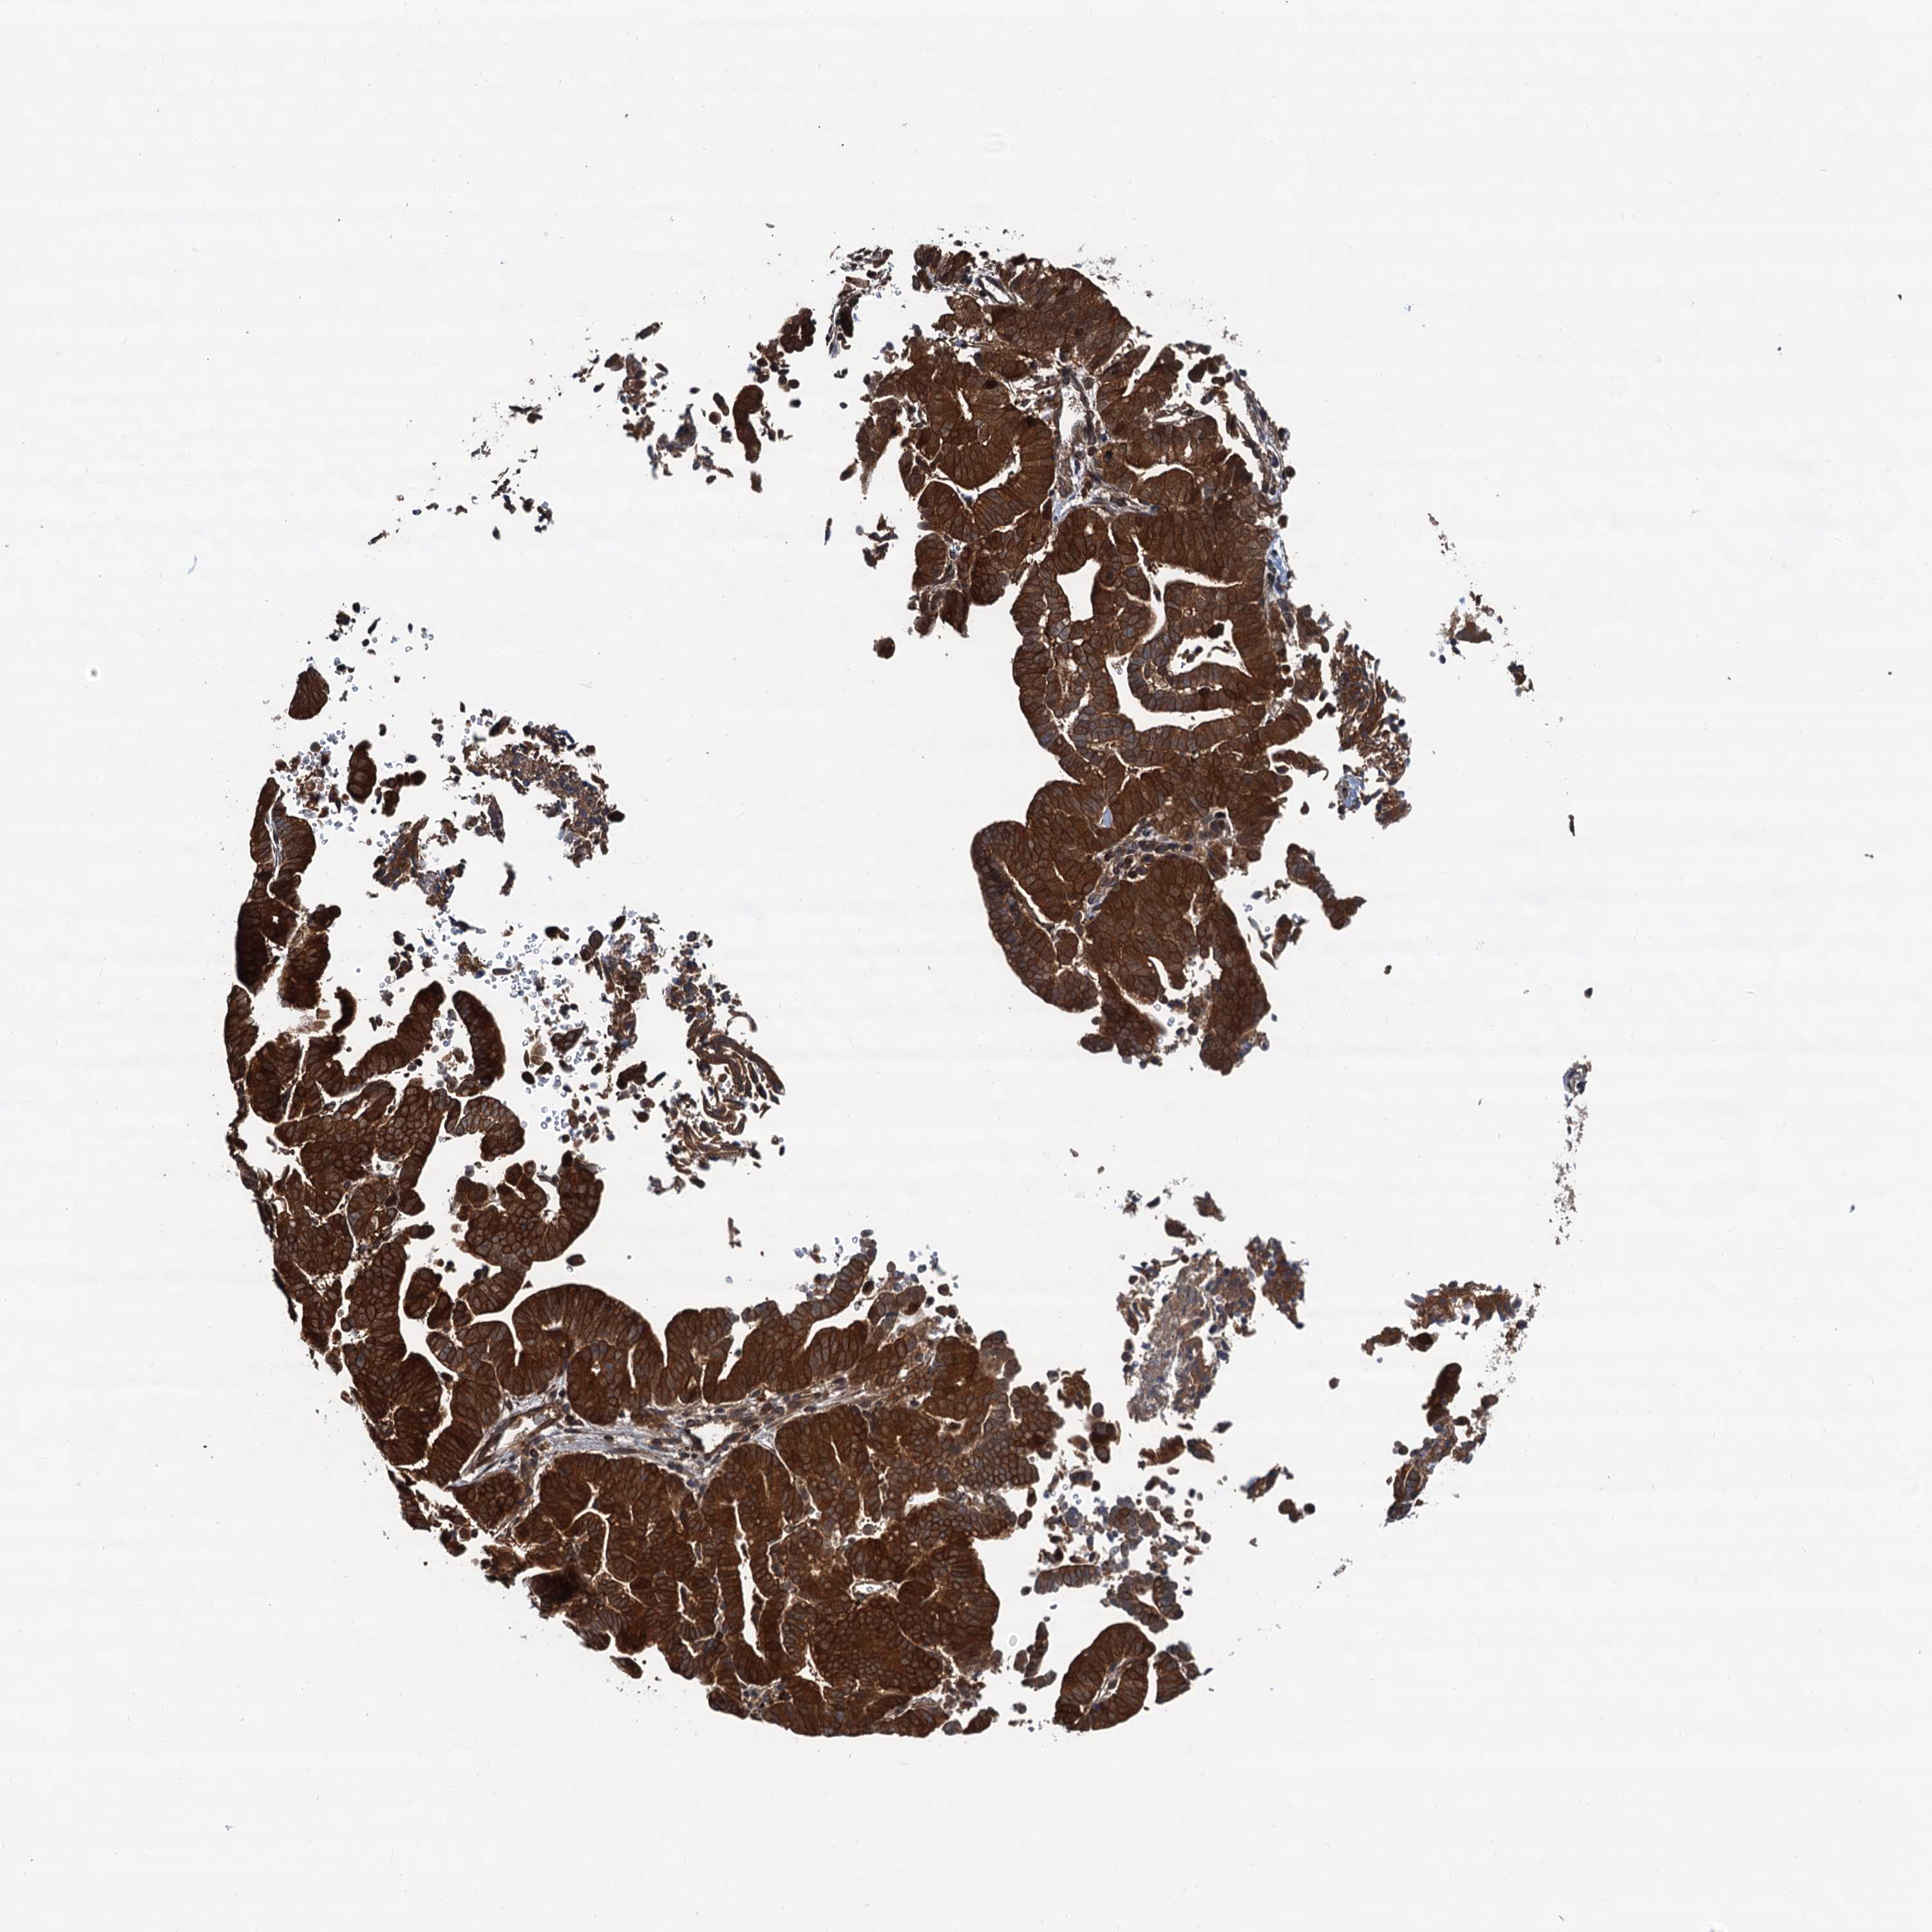

LIVER CANCER - Protein expressioni

A mouse-over function shows sample information and annotation data. Click on an image to view it in a full screen mode. Samples can be filtered based on level of antibody staining by selecting one or several of the following categories: high, medium, low and not detected. The assay and annotation is described here.

Note that samples used for immunohistochemistry by the Human Protein Atlas do not correspond to samples in the TCGA dataset.

Antibody stainingi

Antibody staining in the annotated cell types in the current human tissue is reported as not detected, low, medium, or high, based on conventional immunohistochemistry profiling in selected tissues. This score is based on the combination of the staining intensity and fraction of stained cells.

Each image is clickable and will lead to virtual microscopy that enables deeper exploration of all samples and also displays staining intensity scores, fraction scores and subcellular localization as well as patient and tissue information for each sample.

Antibody HPA039371

Antibody HPA040174

Staining

High

Medium

Low

Not detected

Intensity

Strong

Moderate

Weak

Negative

Quantity

>75%

75%-25%

<25%

None

Location

Nuclear

Cytoplasmic/membranous

Cytoplasmic/membranous,nuclear

Cholangiocarcinoma

Carcinoma, Hepatocellular, NOS